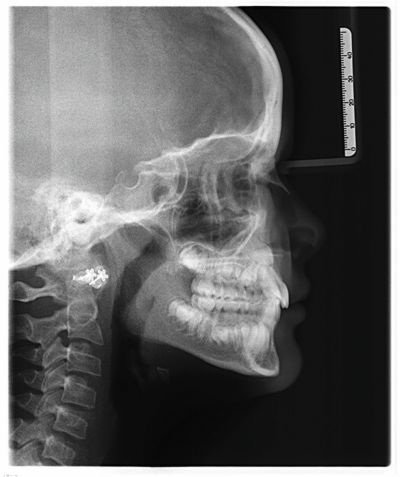

Every orthodontist has a few cases that keep them up at night, where a single tooth seems to have a mind of its own. One recent discussion on the Orthotown message boards centered on a 10-year-old patient (Figs. 1–3) whose upper right canine (UR3) was trying to erupt past the lateral incisor (UR2). The case sparked a lively debate on timing, technique, and just how much Phase I treatment is really worth.

Fig. 2